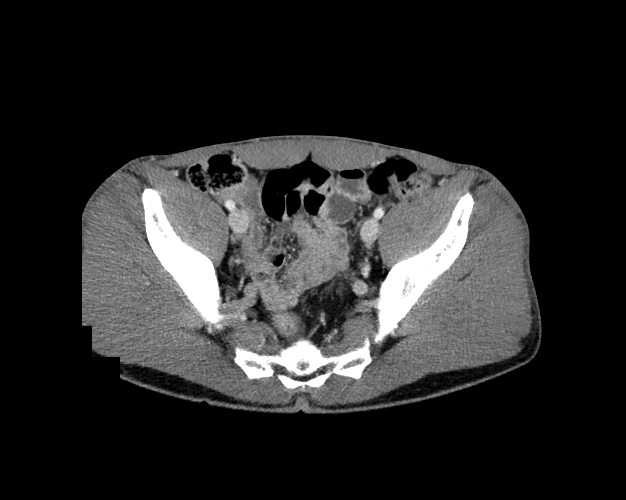

Body

Covers abdominal CT anatomy.

Pelvis

Covers pelvic MRI anatomy.